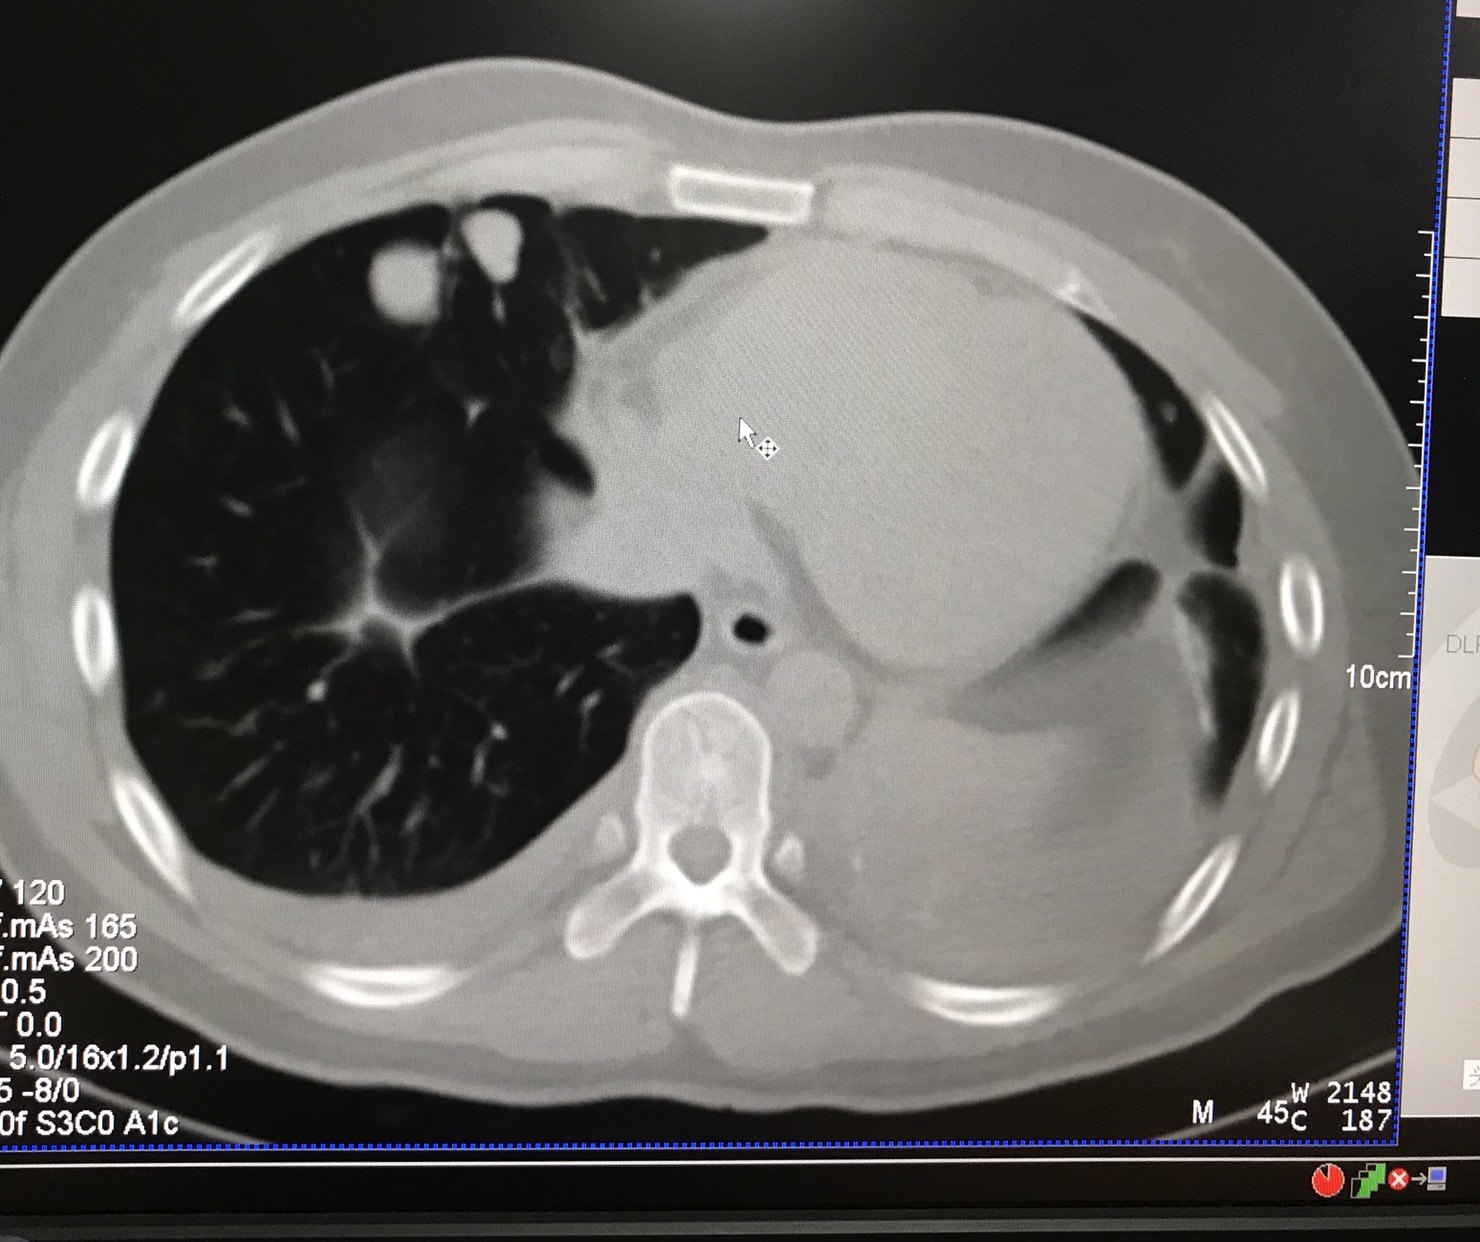

病人女性,64岁,因“咳嗽伴有血性痰和右手臂酸痛”入院。

病人有40年的抽烟史,颈部CT扫描发觉右肺下叶有6.5cmx4.1cm的囊肿。住院前曾被当地诊所确诊有脑部感染,并用药物医治,但没有显著疗效。证实感冒、盗汗等病症,无脑部疾患史。

CT引导下肺叶囊肿细针抽吸细胞学检测显示为:恶性细胞,病理确诊为:肺恶性红色素瘤。